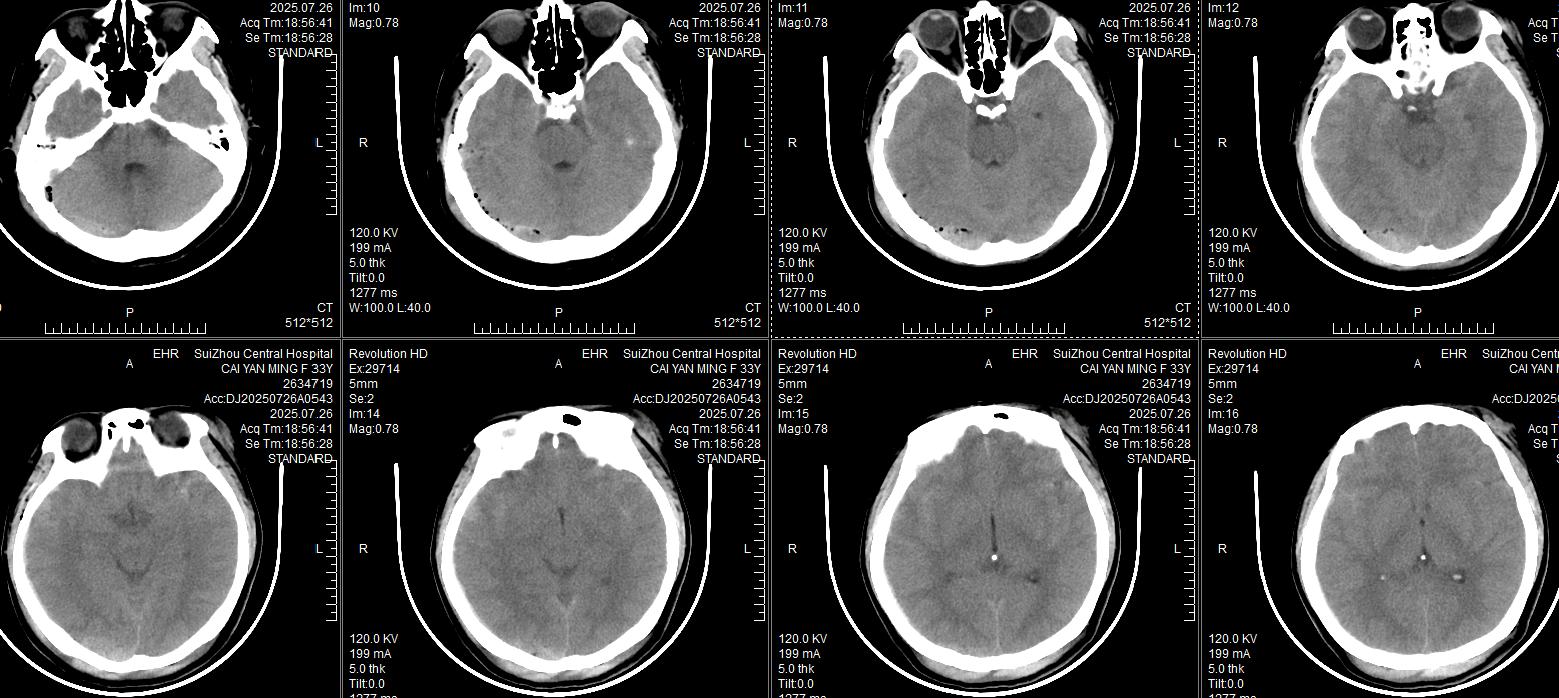

18:56急诊科CT: